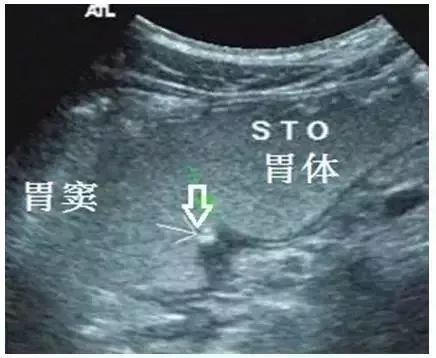

图5 胃角溃疡(愈合期,箭头所示)

2. 愈合期:溃疡深度<3mm,周缘胃壁厚度<5mm,范围<15mm(图5)。